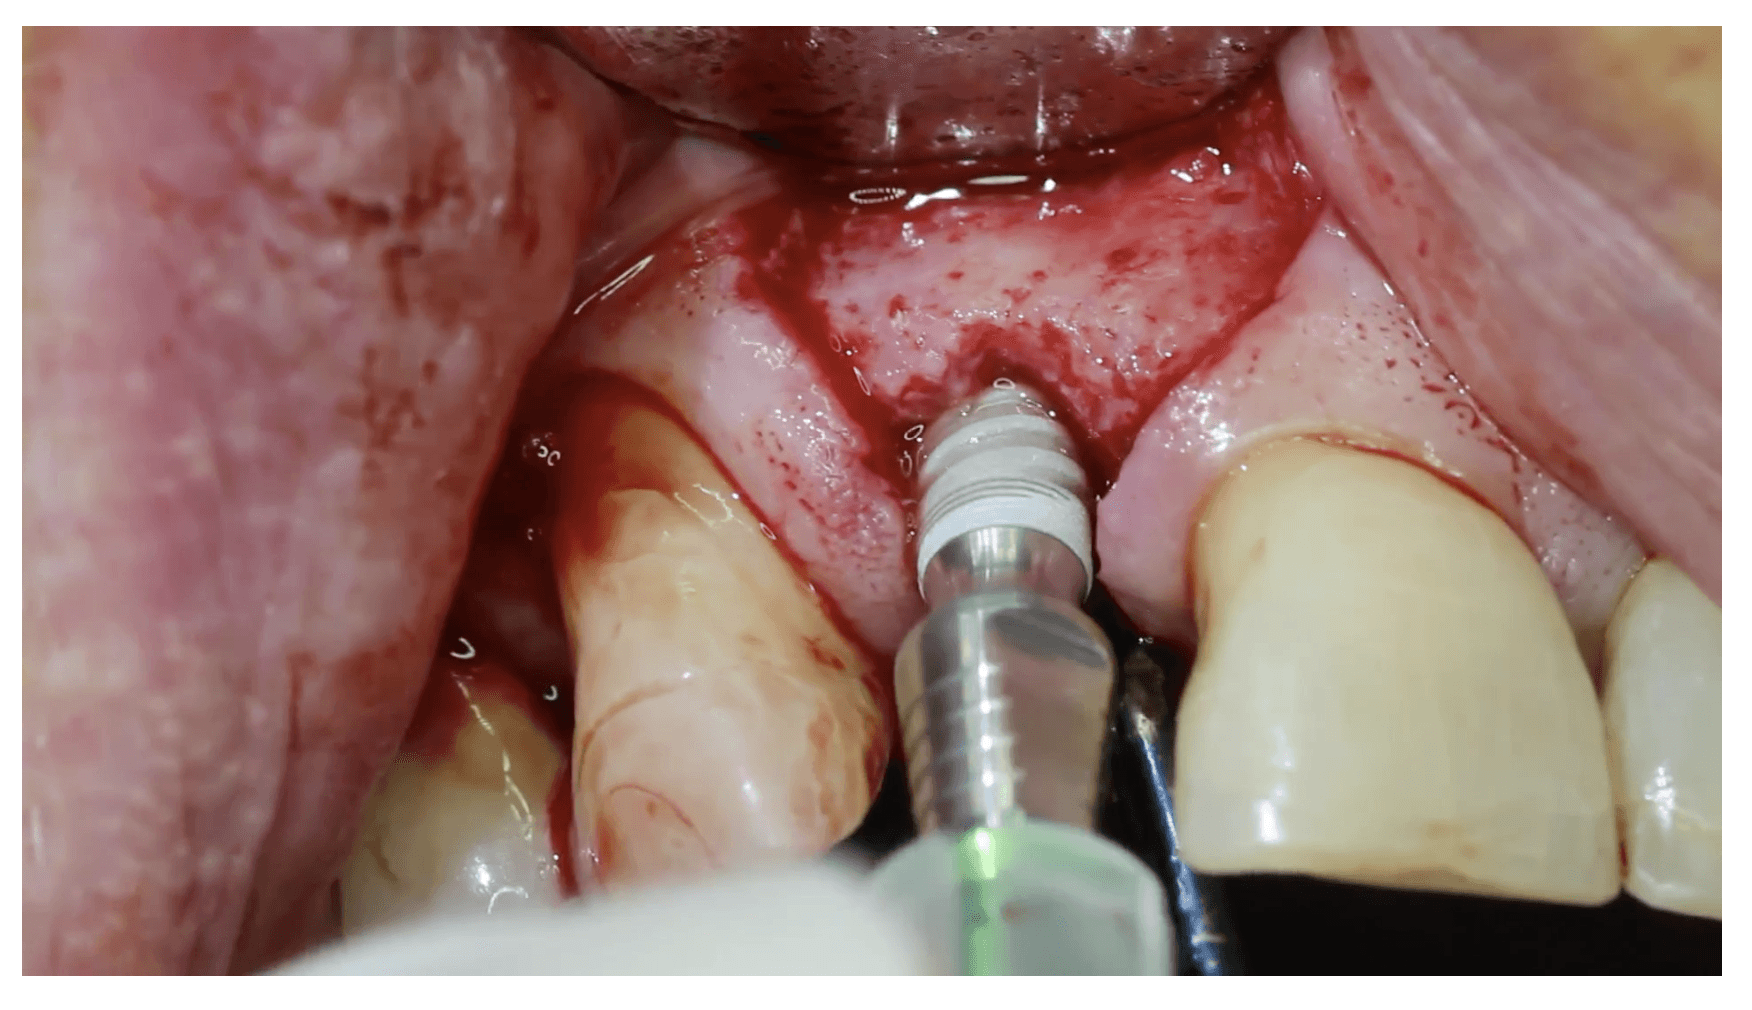

➡️ Step-by-Step Surgical Technique Videos

➡️ Flap Designs for Dental Implants